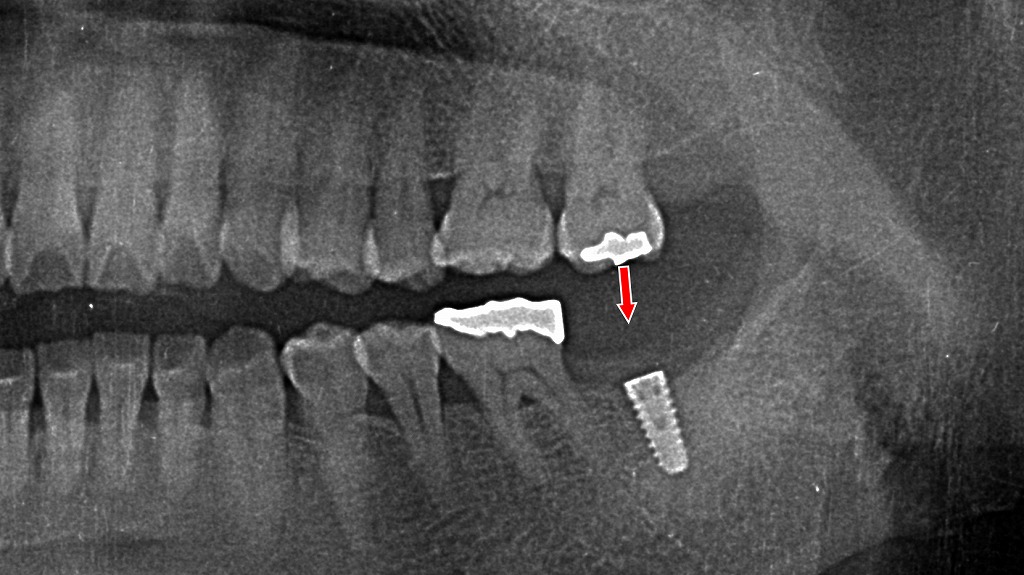

下顎7番抜歯後に起こる変化と対策― 上顎7番の挺出を防ぐための治療経過 ―

下顎7番を抜歯すると、欠損部の歯肉は治癒していきますが、噛み合う相手を失った上顎7番は徐々に挺出しやすくなります。挺出が進行すると、咬合の乱れや将来的な補綴治療の妨げとなる可能性があります。本症例では、抜歯後にインプラントを埋入し、咬合支持を早期に回復することで、上顎7番の挺出を抑制しています。下顎臼歯部の欠損は、周囲や対合歯への影響が大きいため、抜歯後は経過観察だけでなく、将来を見据えた適切な治療選択が重要です。